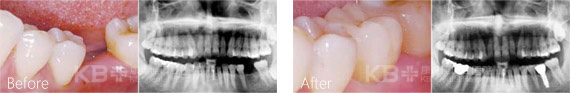

种植牙后依旧抽烟,导致种植牙宣告失败

今年68岁的刘大爷在子女的陪同下来康贝佳做了种植牙修复手术,不料没过多久刘大爷居然发现种植牙有些松动,为此刘大爷急忙复诊。负责种植牙手术的慕林林主任为刘大爷做了详细的口腔检查,检查发现种植牙之所以出现松动现象,主要是因为口腔卫生没有做好导致的。

经过详细的交流刘大爷才说出了实情,原来种完牙后,医生叮嘱刘大爷一定不能抽烟,可是刘大爷烟瘾犯了,瞒着家人隔三差五悄悄抽烟。正是由于刘大爷不听医生的劝告和叮嘱,导致刘大爷的种植牙以失败告终,只能重新进行返工修复。